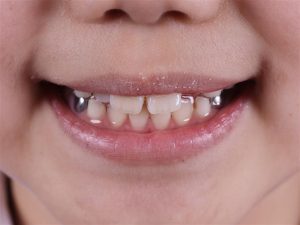

- Khe thưa bất thường: Hai răng cửa chính mọc ra nhưng cách xa nhau (thường >2mm) và không có xu hướng tự khít lại theo thời gian.

- Răng mọc lệch/xoay: Một hoặc cả hai răng cửa bị mọc nghiêng, xoay trục hoặc mọc chìa ra ngoài do bị răng ngầm bên dưới chèn ép.